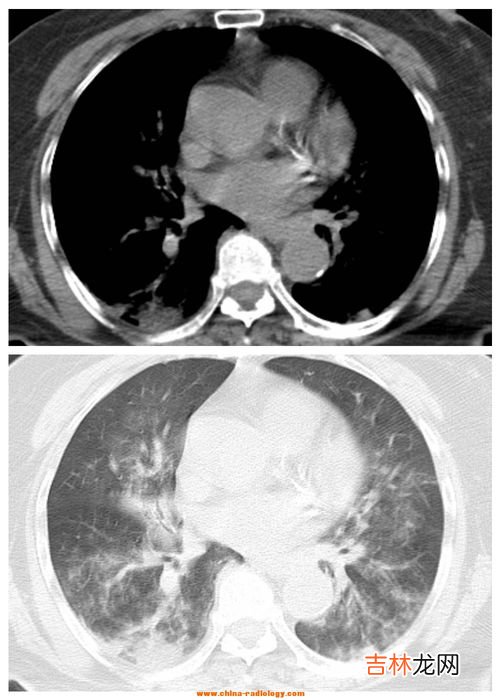

文章插图

3、什么是间质性肺炎间质性肺病(Interstitial lung Disease,简称ILD) 是以弥漫性肺实质、肺泡炎和间质纤维化为病理基本改变,以活动性呼吸困难、X 线胸片示弥漫阴影、限制性通气障碍、弥散功能(DLCO)降低和低氧血症为临床表现的不同类疾病群构成的临床病理实体的总称 。ILD 通常不是恶性的 , 也不是由已知的感染性致病源所引起的 。继发感染时可有黏液浓痰,伴明显消瘦、乏力、厌食、四肢关节痛等全身症状,急性期可伴有发热 。

间质性肺疾病(ILD)是以弥漫性肺实质、肺泡炎症和间质纤维化为病理基本病变,以活动性呼吸困难、X线胸片弥漫性浸润阴影、限制性通气障碍、弥散(DLCO)功能降低和低氧血症为临床表现的不同种类疾病群构成的临床-病理实体的总称 。